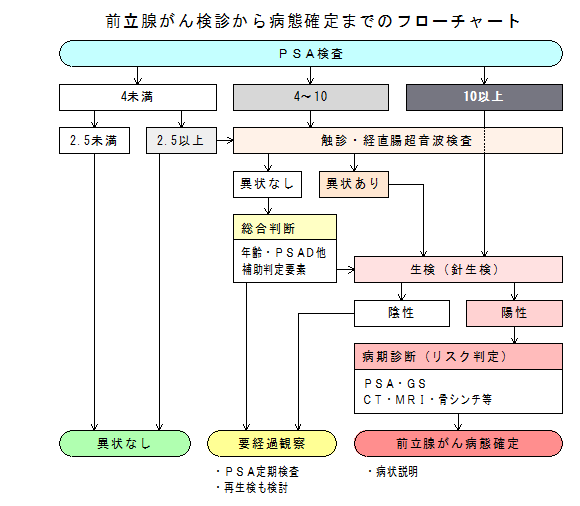

前立腺がんの検査 診断 前立腺がんについて ザイティガ Jp

前立腺がんの検査 画像検査 Ct Mri 骨シンチグラフィ で何がわかる

検査の流れ 50歳を過ぎたら注意 前立腺がん 患者 ご家族の皆様

確定診断までの流れ がんの治療法 詳しく知りたい 前立腺がん

確定診断までの流れ がんの治療法 詳しく知りたい 前立腺がん